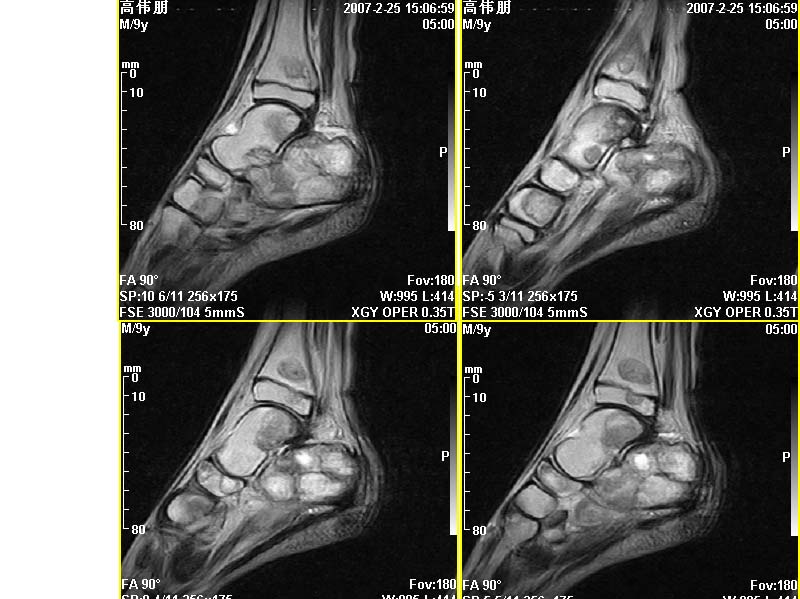

m,9y,左足肿痛半年,无皮肤发红,诱因为外伤后起因。无发烧,无其他疾病。临床考虑多发血管瘤。mri增强后有强化,请分析。是骨髓瘤吗?

左足多发囊状膨胀性骨质破坏,边较清,关节间隙及软组织未见明显异常。结合临床。可排除炎症性病变。病变中心为骨髓腔。有强化。中心坏死。嗜酸性肉芽肿可能大。

多发内生性软骨瘤

结合临床考虑血管瘤侵犯左足骨质。

今天从天津肿瘤医院传来消息:病理结果是非骨化性纤维瘤。